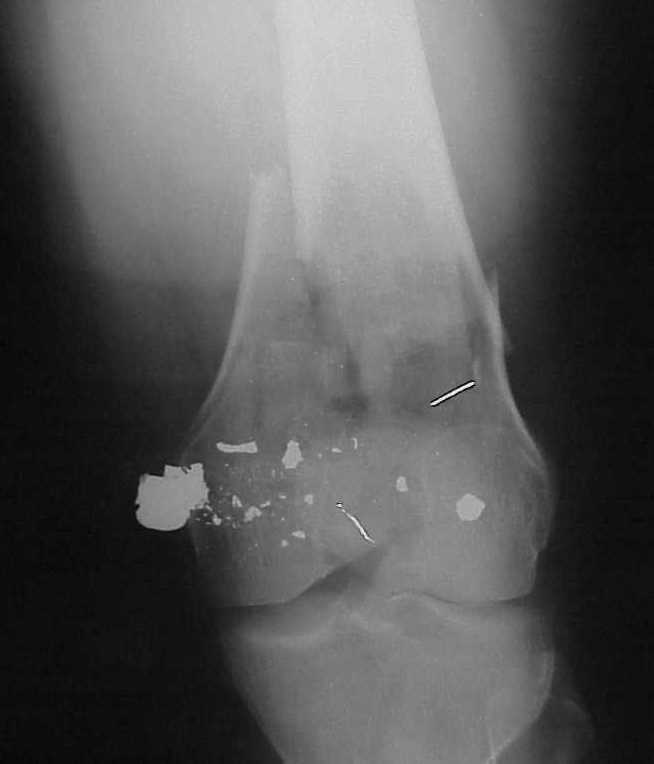

A CT and knee xrays would help identify lateral condyle comminution and/or a "hoffa fragment" of the posterior condyle. I am concerned that the lateral cortex is not sufficient to give purchase for a retrograde IMN. blocking screws could improve this as a possibility. A long blade or LISS if avaible would be my secondary choices. Good luck. Any chance you can get these cases transferred earlier when it

Lateral condyle looks too small for the blade, and the plate too short.

Use 6.5 mm cannulated screws if you have and

place one anterior to where IMN will go if anterior cortex if insufficient and AP screws on either side of the IMN out of the trochlea to provide some additional varus/valgus stability. I worry about the leg going into valgus w/the lack of lateral cortex.

See attached case that was done several years ago before LISS. He had comminuted trochlea and anterior blocking screws were used to prevent anterior IMN cut-out.